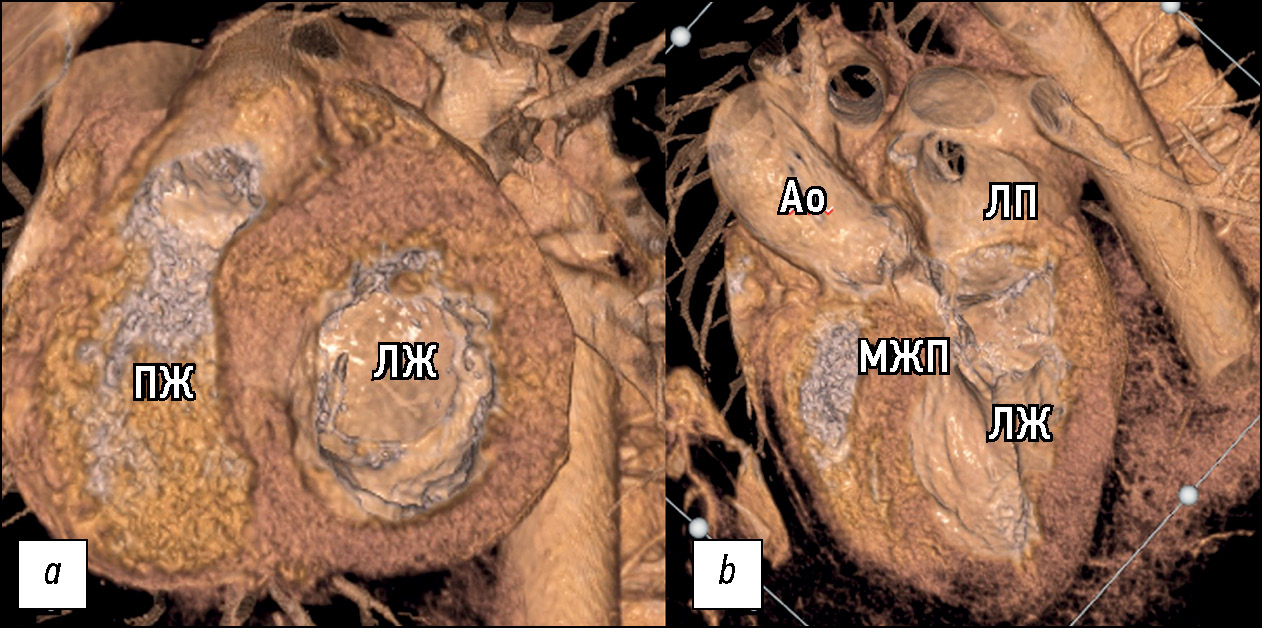

Согласно локализации гипертрофии миокарда ЛЖ по данным КТ были сформированы морфологические варианты ГКМП. Наше исследование демонстрирует вариабельность фенотипических проявлений ГКМП, условно разделённых на 5 морфологических типов и не ограниченных данными вариантами. Большинство — 26 из 47 (55%) — пациентов в нашей работе имели диффузно-септальный морфологический фенотип ГКМП (рис. 4).

Рис. 4. Пример 3D-изображений компьютерной томографии диффузно-септального фенотипа ГКМП: a — плоскость двухкамерной проекции левых отделов сердца; b — короткая ось сердца; c — четырёхкамерная проекция сердца. ЛЖ — левый желудочек, ЛП — левое предсердие, ПЖ — правый желудочек, ПП — правое предсердие.